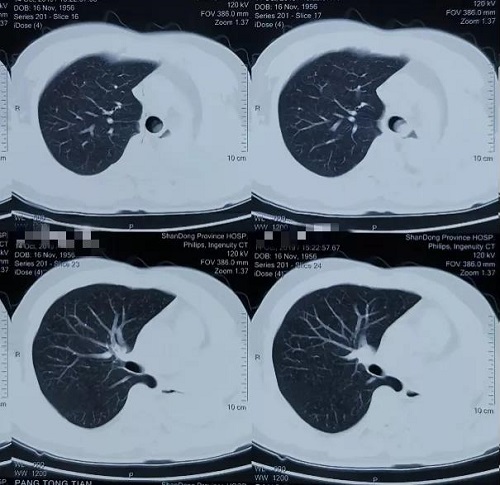

入院时患者胸部CT显示:左肺全切术后残端见新生物生长,且已覆盖隆突,突入气管下段并导致气道中度狭窄。如果不尽快处理,患者呼吸困难会快速进展进而影响生命。

做好充分的术前准备后,在呼吸与危重症医学科主任姜淑娟的指导下,副主任医师龙飞、主治医师王永刚为患者进行手术。气管镜下发现,肿瘤表面血供非常丰富,表面渗血明显,且肿瘤已经越过隆突部分阻塞右主支气管和气管下段。这些表现明确解释了患者术前反复咯血和呼吸困难原因。